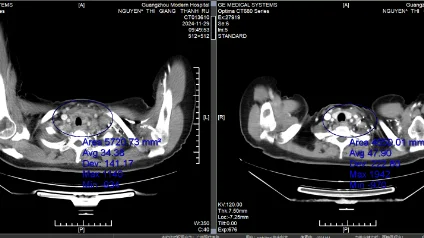

• Hình ảnh CT trước và sau điều trị

Wida

Bệnh nhân Wida (Jakarta, Indonesia) từng bị ung thư buồng trứng trái tái phát giai đoạn IV sau phẫu thuật, kèm theo tình trạng di căn hạch trung thất và hạch dưới đòn.

Sau khi được điều trị bằng phương pháp can thiệp xâm lấn tối thiểu kết hợp với liệu pháp tăng cường miễn dịch, khối u kích thước khoảng 1,4 cm của bà đã hoàn toàn biến mất. Giờ đây, bà không chỉ lấy lại được sức khỏe mà còn đón thêm một bé yêu thông minh.